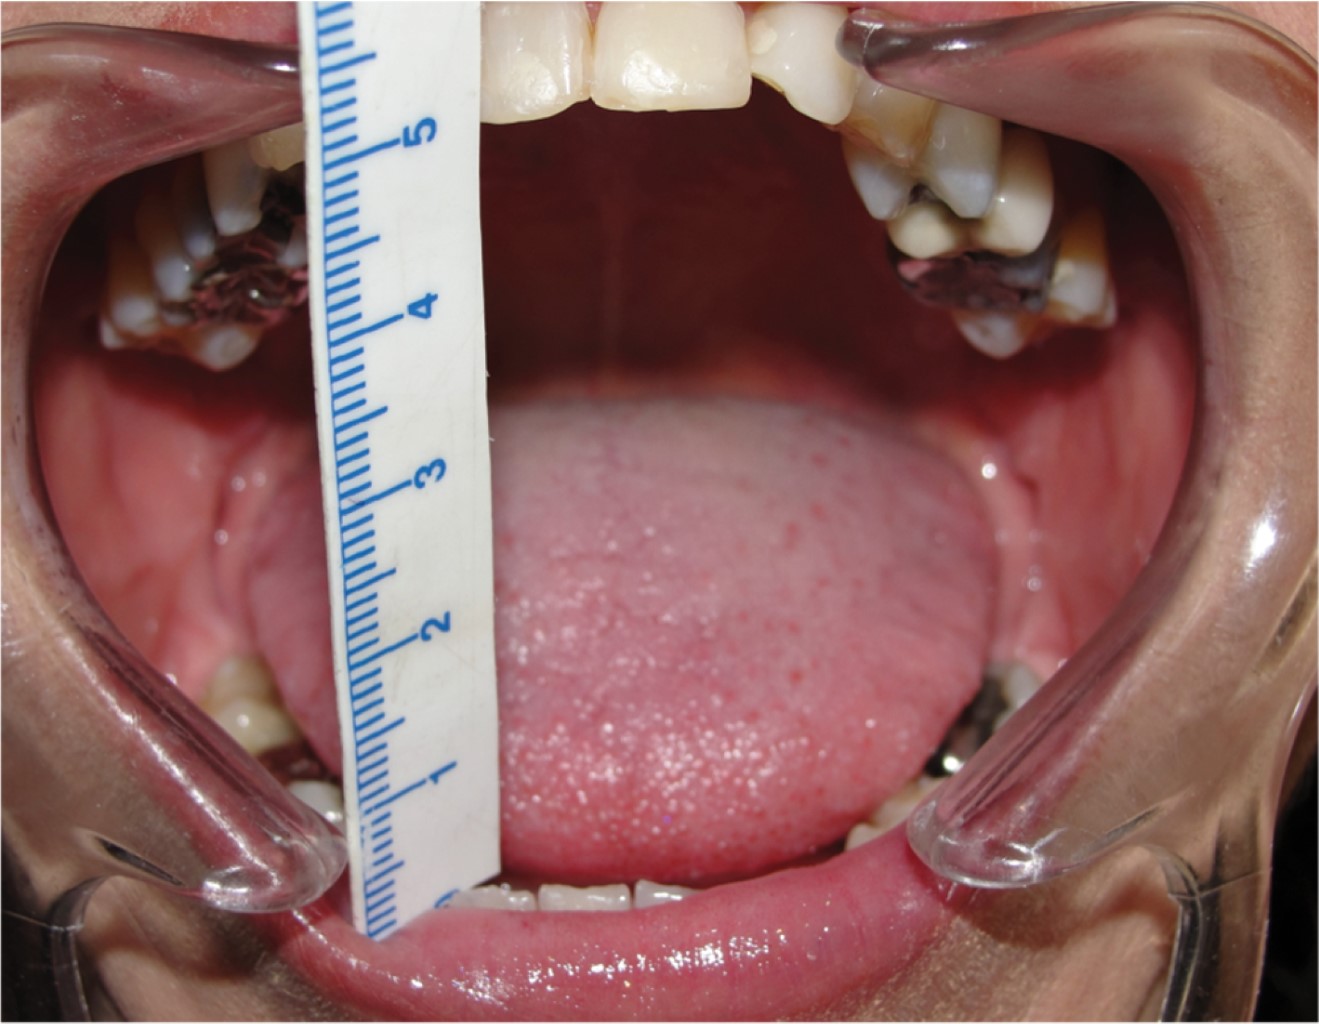

Introduction: the objective is to present a case of total alloplastic replacement of the temporomandibular joint with personalized prostheses (TMJ Concepts®) in rheumatoid arthritis and injection of botulinum toxin type A for protection of prostheses against bruxism. Clinical case: we present the case of a 44-year-old female patient with severe bilateral temporomandibular joint (TMJ) resorption due to advanced stages of rheumatoid arthritis, which was managed by total replacement with a personalized alloplastic prosthesis (TMJ Concepts®, Ventura CA) and infiltration of botulinum toxin type A (Botox, Allergan, Ireland). Results: painful symptomatology was eliminated immediately and pre-surgical oral opening changes from 2 to 50 mm were achieved in the first year after botulinum toxin placement; 12 years later, the prosthesis is stable and functional. Conclusions: botulinum toxin can be a simple, safe, and effective adjuvant treatment in patients reconstructed with personalized alloplastic prostheses.

Figure 1